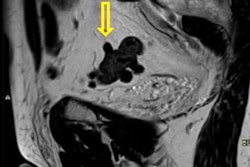

When evaluating prostate MRI scans, radiologists can detect some clinically significant genitourinary and nongenitourinary incidental findings, and they need to look beyond the prostate and accurately recognize and characterize these findings.

That's the main message from an experienced group of radiologists in Bilbao, Spain. They've produced a useful checklist of incidental findings to look out for, and they've also provided four clinical cases that you can learn from. Don't miss our news report.